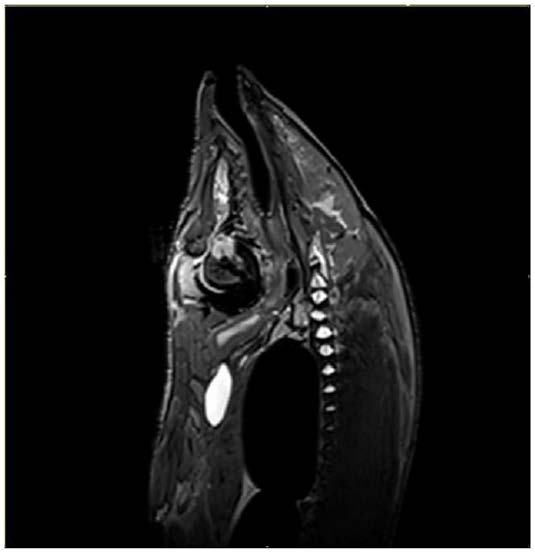

步骤5,进行磁共振扫描,确定扫描平面、层厚、层数和扫描视野参数;

步骤6,在矢状位磁共振图像中测量两眼球连线中点到冠状划痕的距离;

步骤7,在轴状位磁共振图像中测量两眼球连线中点到脑电极植入位点的距离;

2.根据权利要求1所述的一种将鲤鱼磁共振扫描坐标转换为脑立体定位坐标的方法,其特征在于:步骤5中,将鲤鱼固定在磁共振成像仪的膝关节线圈内,鲤鱼呈俯卧位、头先进,进床前使磁共振扫描十字线对准颅脑中心;然后在定位项图像中确定矢状位扫描平面,扫描时,矢状位扫描平面与YOZ平面平行,矢状位成像MR获取方式为3D,成像序列选用T2WI快速自旋回波扫描序列,重复时间TR=750ms,回波时间TE=112ms,层厚=0.8mm,层数=

72,视野FOV为200×200mm2,空间分辨率为512×512,旋转角度FA=170°,平均次数NEX=1,回波链长度ETL=21,获取时间TA=442s。

3.根据权利要求1所述的一种将鲤鱼磁共振扫描坐标转换为脑立体定位坐标的方法,其特征在于:步骤5中,在矢状位扫描平面中确定轴状位扫描平面,扫描时,将轴状位扫描平面与XOY平面平行,并使视野框的上边界与颅骨表面的Y坐标轴吻合,轴状位成像MR获取方式为3D,成像序列选用T2WI自旋回波序列,重复时间TR=1000ms,回波时间TE=131ms,层厚=0.5mm,层数=56,视野FOV为119×119mm2,空间分辨率为512×512,旋转角度FA=120°,平均次数NEX=2,回波链长度ETL=65,获取时间TA=256s。